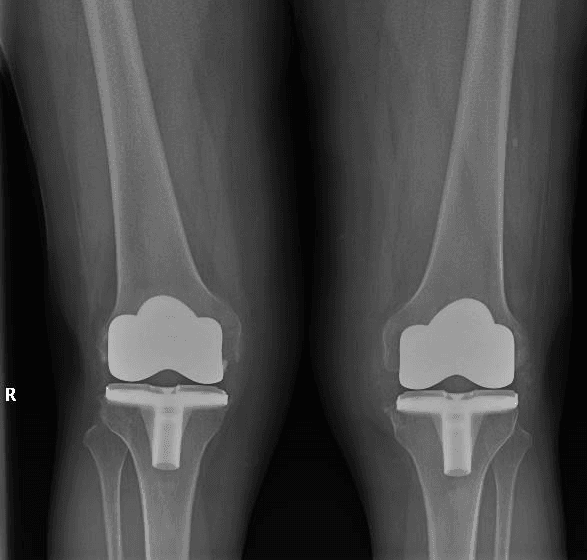

L’intervento di artroprotesi di ginocchio prevede la sostituzione chirurgica del femore distale e della tibia prossimale con protesi metalliche, associate a materiali plastici e/o ceramici. Quando necessario, si può includere anche la protesizzazione della rotula. Lo scopo principale di questa procedura è ripristinare un’articolazione stabile e funzionale, migliorando la capacità di movimento del paziente e alleviando il dolore, con conseguente miglioramento della qualità della vita.

Oggi sono disponibili diversi tipi di protesi, adattabili alle varie esigenze funzionali dei pazienti e ai diversi scenari osseo-legamentosi. Per le protesi totali si distinguono in generale impianti con conservazione (Cruciate Retaining – CR) o sacrificio (Posterior Stabilized – PS) del legamento crociato posteriore, con ulteriori sottogruppi di inserti a seconda delle necessità del paziente e della tecnica di impianto adottata. Per situazioni più complesse o per revisioni protesiche si possono utilizzare impianti semivincolati o a cerniera.

Negli ultimi dieci anni, il numero di interventi di sostituzione protesica del ginocchio è aumentato significativamente, quasi eguagliando quello delle sostituzioni d’anca. Secondo il Registro Italiano Artroprotesi (RIAP), in Italia si effettuano circa 27.000 interventi di sostituzione primaria del ginocchio ogni anno.